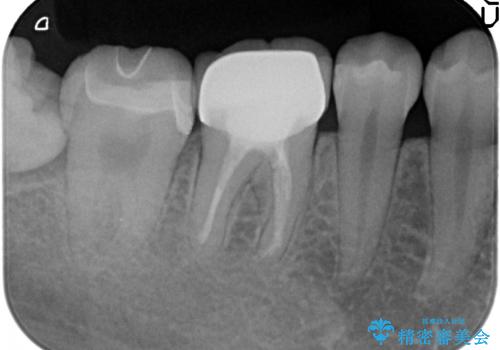

- 右下7の銀歯を白くしたいといらっしゃった方の症例です。

銀歯及び虫歯を除去後、セラミックインレーで修復を行いました。

当院のセラミックインレーはemaxという強度と審美性に優れた材料を使用しています。

またプレス方式でインレーを製作しているため、削り出しで製作するCADCAMより優れた適合性も持ち合わせており、虫歯が再発しにくい修復物です。